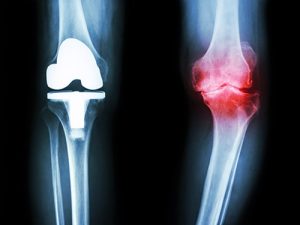

Виды эндопротезирования

В клинике СТС осуществляется замена таких суставов:

Последние достижения исследователей позволили создавать протезы, которые анатомически приближены природным суставам. Протез состоит из нескольких составляющих: головки, ножки и чашки.

В настоящее время используются импланты, которые обладают устойчивостью к нагрузкам, износоустойчивостью, они выполняются из биосовместимых материалов. Большое значение имеет фактор той амплитуды движений, который может обеспечить протез.

Протез может быть выполнен из керамики, металла, специального высокомолекулярного полиэтилена. Наиболее востребованным видом имплантов является протез, у которого чашечка выполнена из высокомолекулярного полиэтилена, а головка выполнена – из металла. Эта конструкция позволяет выдерживать настолько высокие нагрузки, что его можно имплантировать даже людям, которые ведут активный образ жизни и планируют заниматься спортом. Они долговечны и могут прослужить до тридцати лет, к тому же, имеют умеренную цену.

Вид эндопротезирования определяется степенью поражения сустава. В частности, в клинике СТС могут быть проведены следующие виды замены сустава:

Тотальное. Если весь сустав разрушен и его невозможно восстановить, его заменяют полностью. Имплант имитирует естественный сустав, имеет такие составляющие: ножку с покрытием из титана и пористым покрытием, головку из металла и суставную впадину (из полимера).